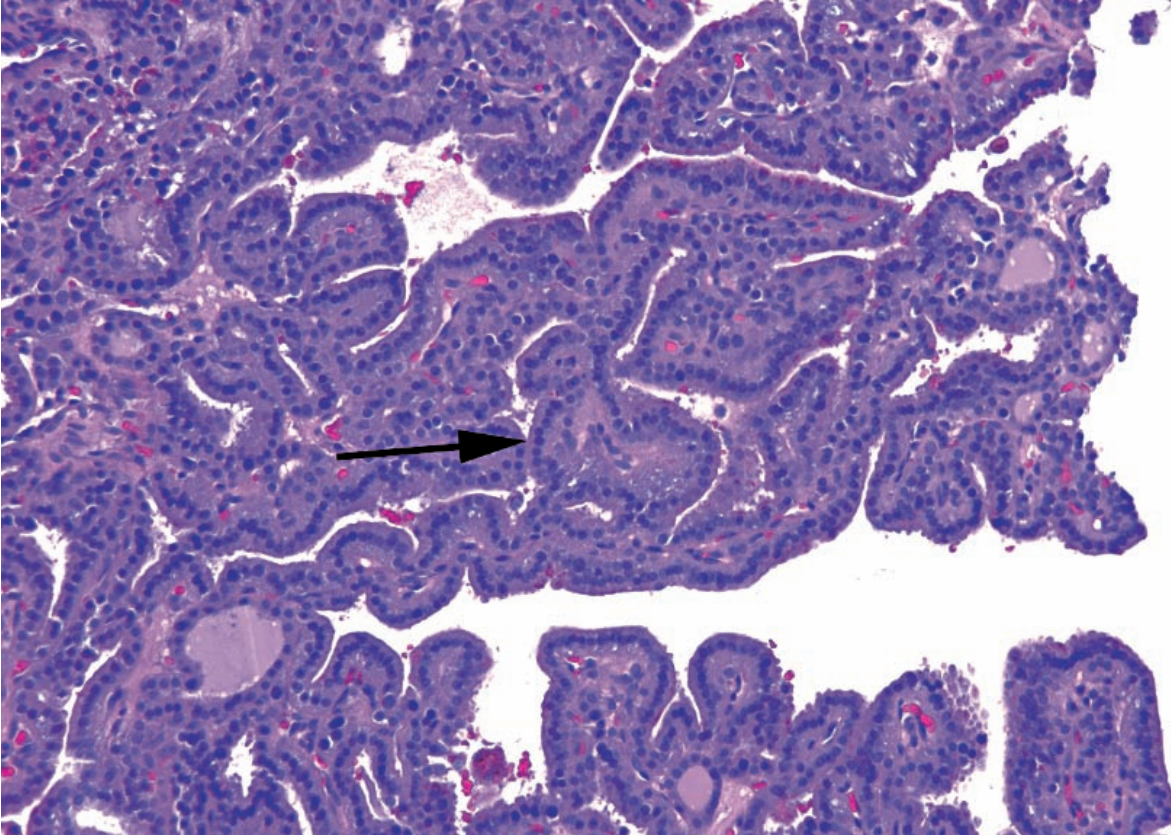

Untreated: Highly cellular thyroid with minimal colloid.

Treated: Large follicles with prominent papillary infoldings and scalloped colloid.

A

Grave’s Disease

Arrow: Papillary infoldings of follicular epithelium